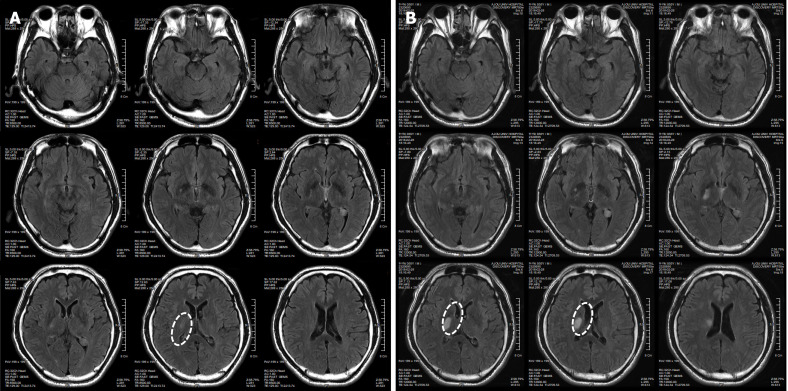

患者于2018年2月17日至18日出現暫時(shí)性無(wú)力癥狀,早上醒來(lái)后突發(fā)急性中風(fēng),導致左上肢和下肢癱瘓?;颊咴诖髮W(xué)醫院急診室被診斷為Rt紋狀體囊性梗死(圖1A)。他于2018年3月2日出院,僅接受了阿司匹林處方,因為根據腦計算機斷層掃描 (CT) 掃描,他的腦血管正常,盡管他的病情在住院期間惡化(圖1)。出院當天,他被送往康復專(zhuān)科醫院接受長(cháng)期康復治療。然后他于2018年3月13日來(lái)韓國首爾生物美容與健康公司 (bBHC)-干細胞治療與研究所 (STRI)接受干細胞治療。

圖1:微創(chuàng  )人臍帶間充質(zhì)干細胞移植前患者的腦部計算機斷層掃描圖像。

患者在干細胞移植后約30個(gè)月拍攝腦部CT圖像以確認病灶的大小。病灶縮小至0.6cm×0.3cm(圖4)。

圖4:微創(chuàng  )人臍帶間充質(zhì)干細胞移植后患者的腦部計算機斷層掃描圖像。